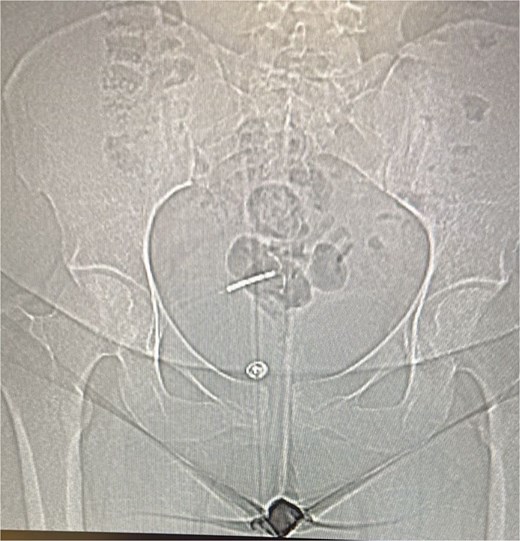

Initial laboratory work-up revealed a normal white blood cell count. Urinalysis was positive for leukocytes and nitrites, indicating a urinary tract infection. A plain abdominal X-ray did not clearly visualize the IUD but raised suspicion for its extrauterine location (Fig. 1).

A plain abdominal X-ray was performed, which visualize the IUD with suspicion for its extrauterine location.